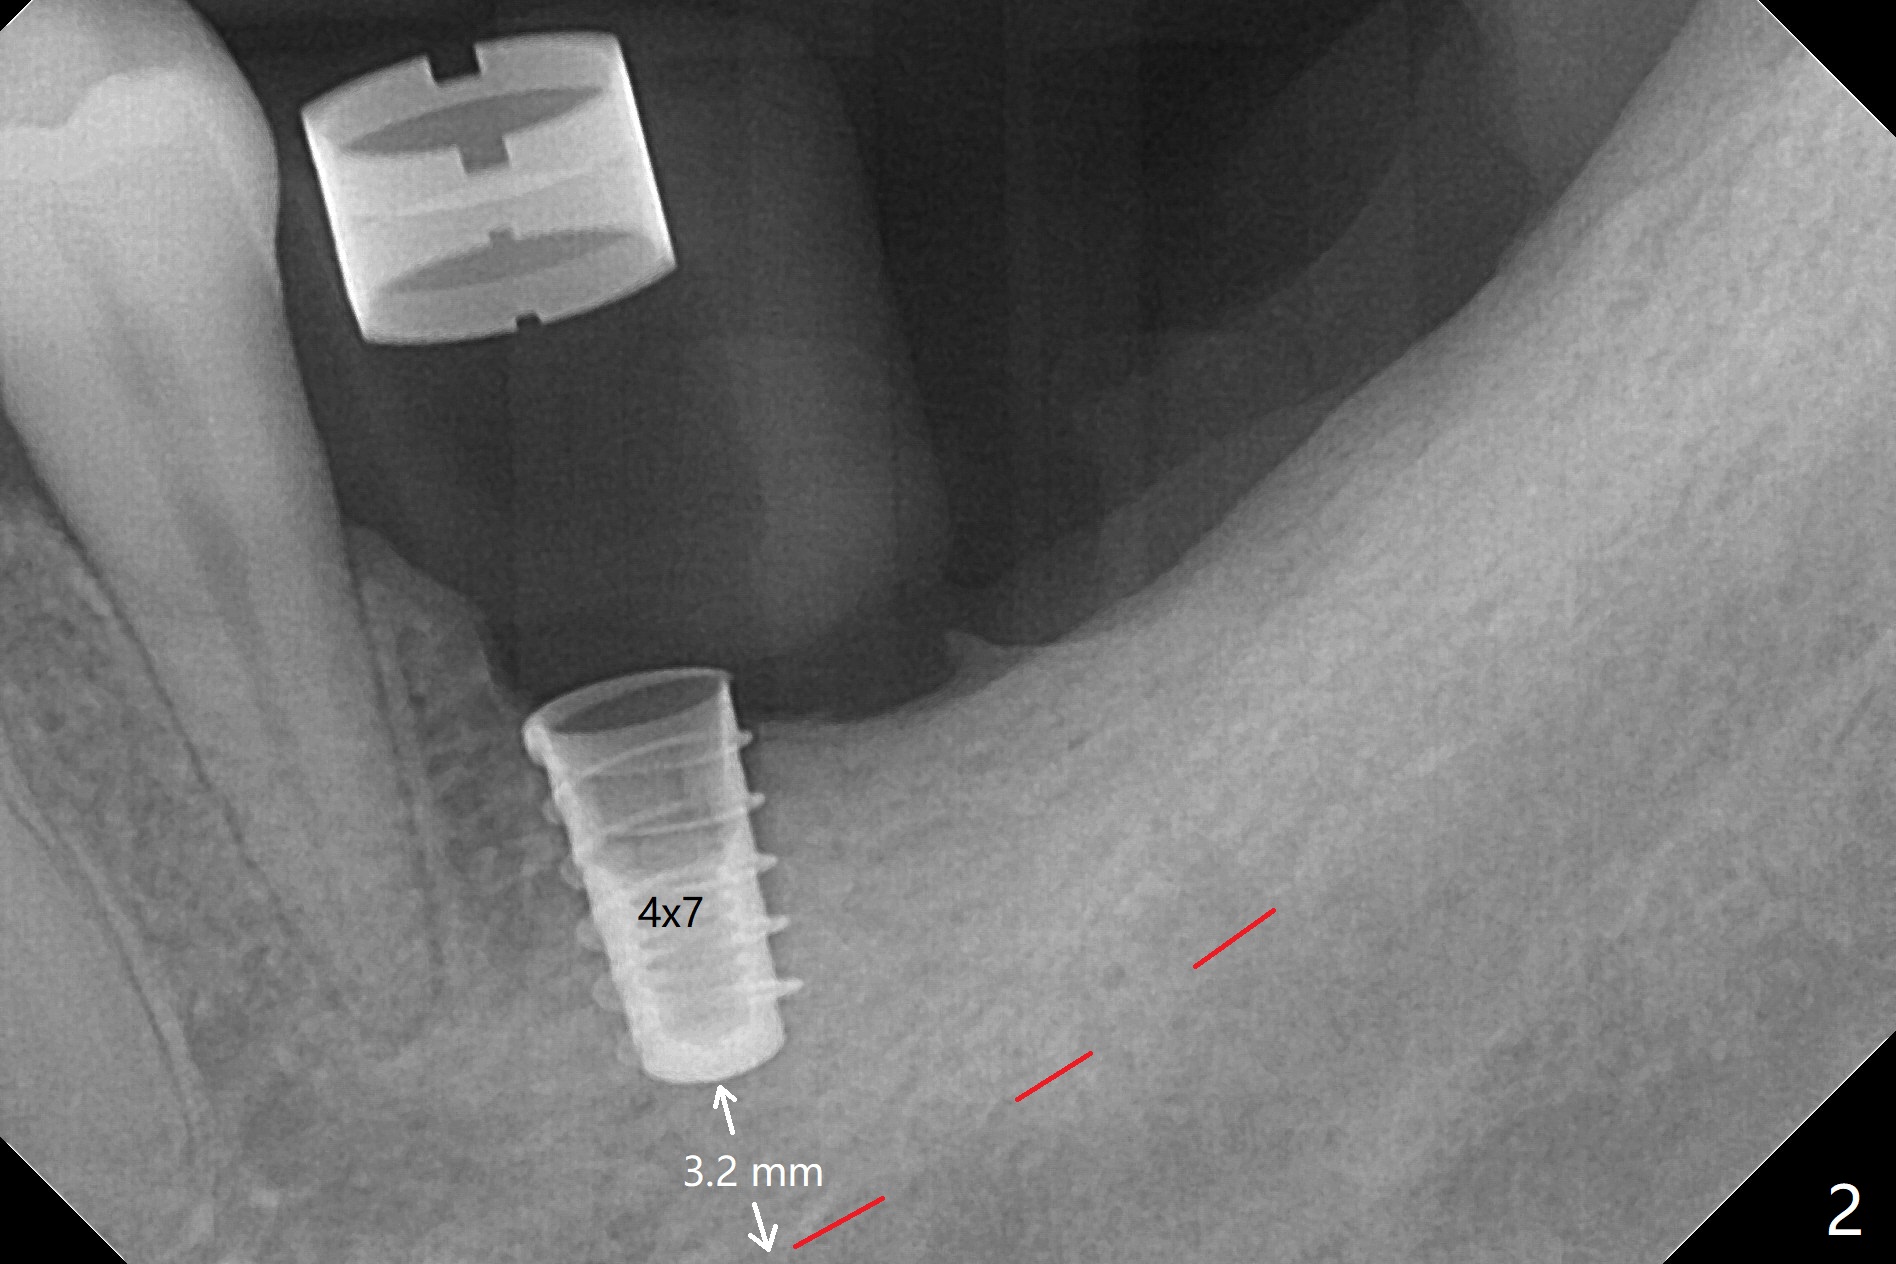

After use of 4x7.3 mm drill with guide, the buccal osteotomy height is 4 mm at #19, unsuitable for 4x5 mm Bicon implant, which requires 3 mm subcrestal placement. PA shows 4.3 mm bone from the Inferior Alveolar Canal (IAC, red dashed line (the superior border)). Following 4x8.5 mm drill, a 4x7 mm IBS implant is placed with distobuccal thread exposure and 3.2 mm clearance from IAC. With 3.5x10 mm drill less full length, the implant is placed a little deeper (10 Ncm). Bleeding spots created (Fig.3), sticky bone (cortical, fine granule) is placed (Fig.4 *), which is covered with PRF membrane and Colla tape. 4-0 PGA is used. There is no postop paresthesia. The length discrepancy is probably due to distal free end guide, which produces mesial placement of the implant. Try to make a premolar-sized crown. Use profile drill in uncover.